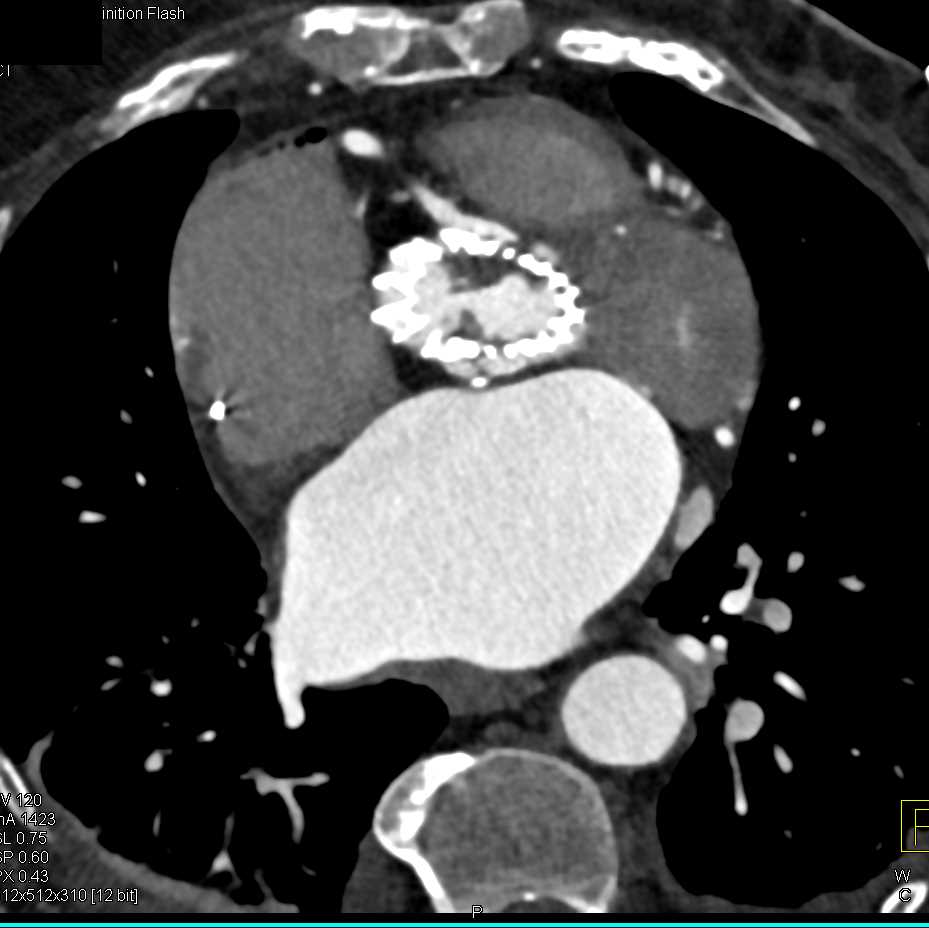

Papillary Fibroelastoma off the Aortic Valve